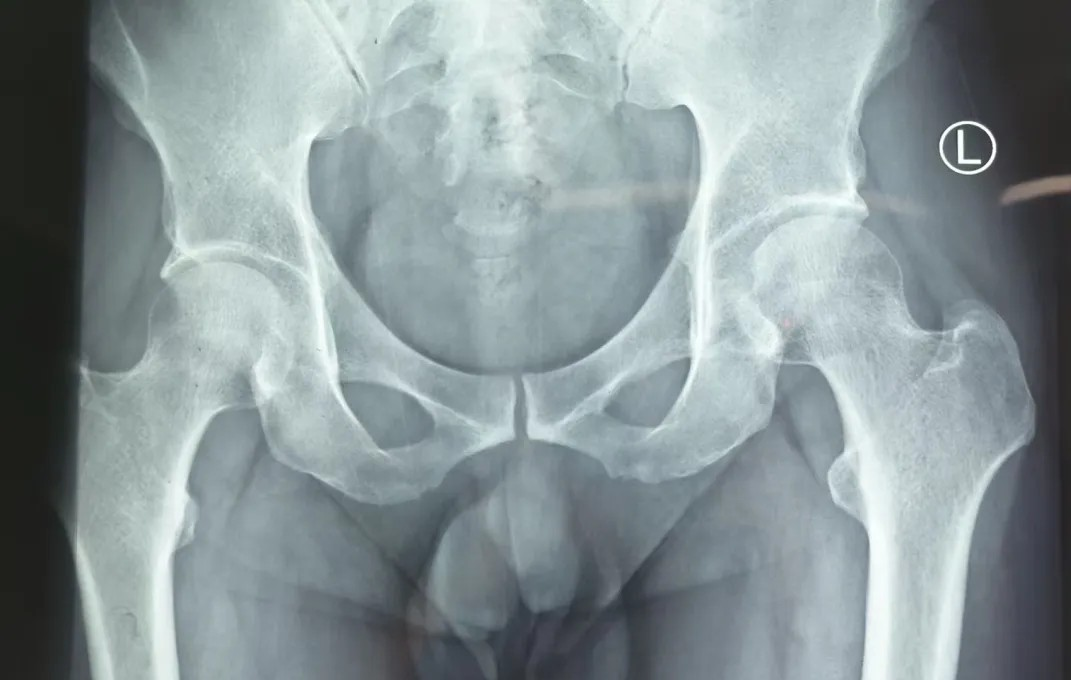

股骨头坏死早期症状不典型,很容易和 “腰腿痛”“关节炎” 混淆,加上一般的X线检查不易发现早期的股骨头坏死,许多患者因此耽误治疗。当身体出现以下表现时,不要忽视:

病情处于早期,一般尝试一些非手术的方法来延缓病情进展。如通过减少负重(避免扛重物、少爬楼梯)、局部理疗(冲击波、超声波),再配合改善血液循环的药物,大部分人能阻止病情进展。